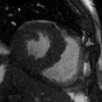

Supervised Deep-Learning (DL)-based reconstruction algorithms have shown state-of-the-art results for highly-undersampled dynamic Magnetic Resonance Imaging (MRI) reconstruction. However, the requirement of excessive high-quality ground-truth data hinders their applications due to the generalization problem. Recently, Implicit Neural Representation (INR) has appeared as a powerful DL-based tool for solving the inverse problem by characterizing the attributes of a signal as a continuous function of corresponding coordinates in an unsupervised manner. In this work, we proposed an INR-based method to improve dynamic MRI reconstruction from highly undersampled k-space data, which only takes spatiotemporal coordinates as inputs. Specifically, the proposed INR represents the dynamic MRI images as an implicit function and encodes them into neural networks. The weights of the network are learned from sparsely-acquired (k, t)-space data itself only, without external training datasets or prior images. Benefiting from the strong implicit continuity regularization of INR together with explicit regularization for low-rankness and sparsity, our proposed method outperforms the compared scan-specific methods at various acceleration factors. E.g., experiments on retrospective cardiac cine datasets show an improvement of 5.5 ~ 7.1 dB in PSNR for extremely high accelerations (up to 41.6-fold). The high-quality and inner continuity of the images provided by INR has great potential to further improve the spatiotemporal resolution of dynamic MRI, without the need of any training data.

翻译:在这项工作中,我们建议了一种基于IRI的方法,用这种方法来改进动态磁共振感应成像(MRI)重建,而该方法只是以高度低劣的 k-空间数据为基础,而该数据仅以磁共振坐标作为投入。具体地说,拟议的IRI将动态MRI图像作为一种隐含功能来表示,并将其编码到神经网络中。网络的权重仅从稀有的(k, t)空间数据本身中学习,而没有外部培训数据集或先前的图像。 利用基于IRI的强有力隐含性稳定化,同时不以清晰的动态和时空坐标坐标坐标坐标坐标作为投入。 拟议的IRIR将动态MRI图像作为一种隐含功能,将其编码到神经网络中。网络的权重仅从淡化的(k, t)空间数据本身学习,而没有外部培训数据集或先前的图像。